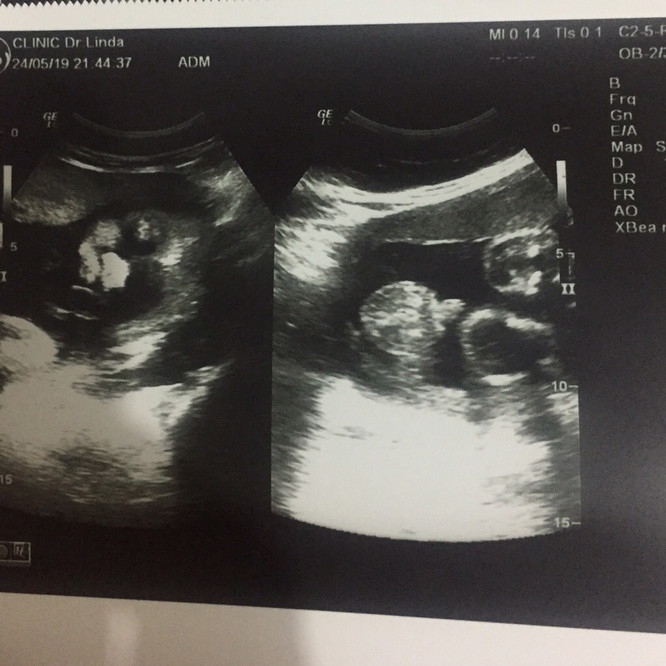

30week ผู้ชายค่ะ

30W1D ผู้ชายค่ะ